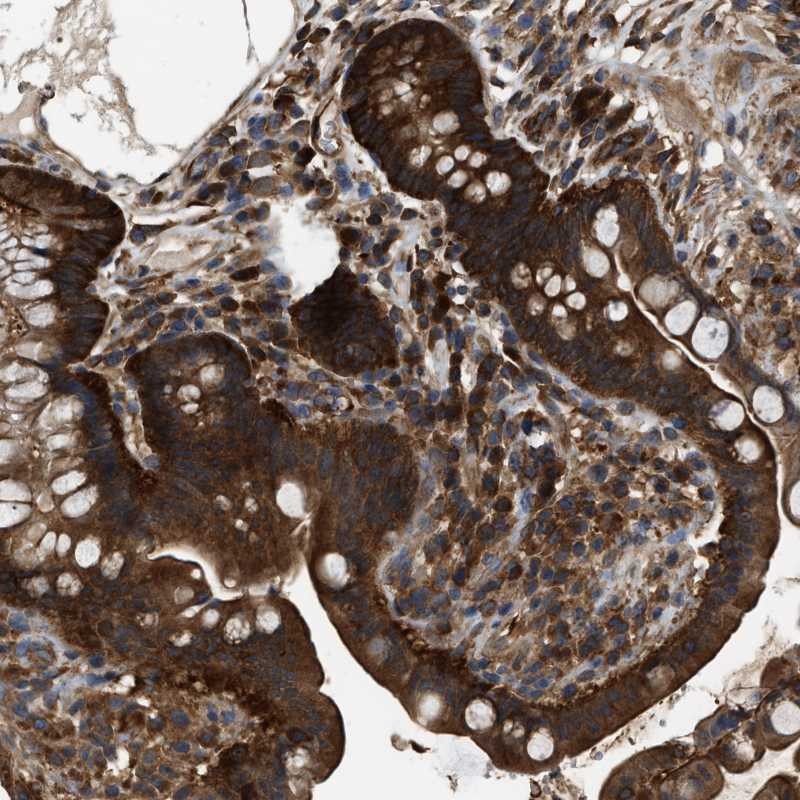

Immunohistochemical staining of human colon shows strong cytoplasmic positivity in glandular cells.